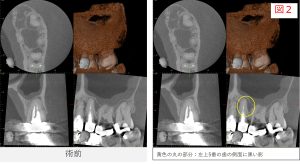

紹介時の画像診断では、左上7番だけでなく、左上5番の根の先にも黒い影が見られました。

●レントゲン・CT画像所見

レントゲンおよびCT画像では、左上5番の根尖部に透過像(骨のない部分)が確認されました。

根管充填後は、症状の有無だけでなく、レントゲンやCT画像を用いて根の先や側面の骨の状態を確認しながら経過を観察していきます。

- レントゲンおよびCTで確認したところ、根の先や側面に見られていた透過像は縮小し、骨の回復傾向が確認されました。

- 特に、根の側面に見られていた透過像は、歯の根の途中から分かれている細い枝状の通路(側枝:そくし)に関連した炎症であった可能性が考えられます。

こうした側枝に感染が及んでいる場合、レントゲンやCTでは根の側面に黒い影として見えることがあります。

- 今回の症例では、根管治療後の経過観察でその透過像が縮小し、骨の回復傾向が確認されました。